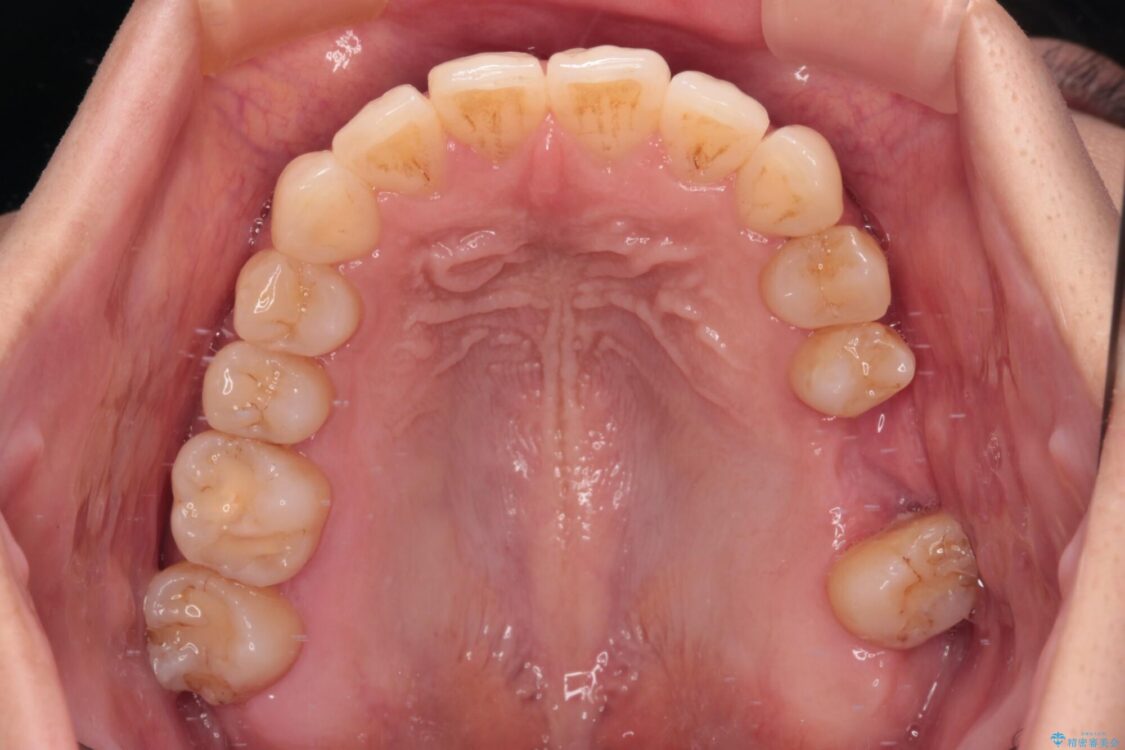

治療途中

• インビザラインによる矯正治療と奥歯のインプラント治療 治療途中画像